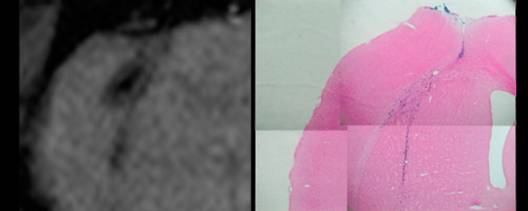

図3

図3 ラット脳内のMR標識PC12細胞。

T2*-強調画像(200/30、45)(左)とPrussian Blueによる鉄染色(右)。標識PC12細胞は線条体へ移植し、61日後にMR画像を撮像した(左)。その後、脳組織を固定して鉄染色の後、写真(右)を得た。

このようにして調整した標識細胞を動物に移植し、MR画像による生体中からの検出を試みた。ここでは、標識PC12 細胞をラット脳の線条体へ移植した例を示している (図3)。この実験では、線条体に移植された細胞がT2*-強調画像により、3分程度のMR画像撮影時間で、画像コントラストから明瞭に識別される。さらに、この細胞の一部はおよそ9週間の間に、脳梁に沿って再分布していることが分かる。従ってHVJ-Eは比較検討した市販の遺伝子導入剤に比べ、きわめて効率よくMR標識剤を細胞内に移動させることができるため、生体内での標識細胞の部位を示すMRIの画像コントラストも顕著になり、標識細胞を長期にわたって継続的に観察することができるようになった。もちろん、本方法におけるHVJ-Eと造影剤の組み合わせでは、細胞に対する毒性も少なく、MR標識を施した後も、無標識の細胞と同様の増殖性を示し、また、脳組織の中でも細胞の機能を失うことはなかった。継続観察の最後に脳を固定して標本を作製し、鉄染色を行ったところ(図1、右図)、MR画像ときわめて良い一致を示した。このことからも、この常磁性標識が生体内での細胞の位置を正確に反映し、実験動物を犠牲にすることなく、長期間継続して移植細胞を観察できるようになった。